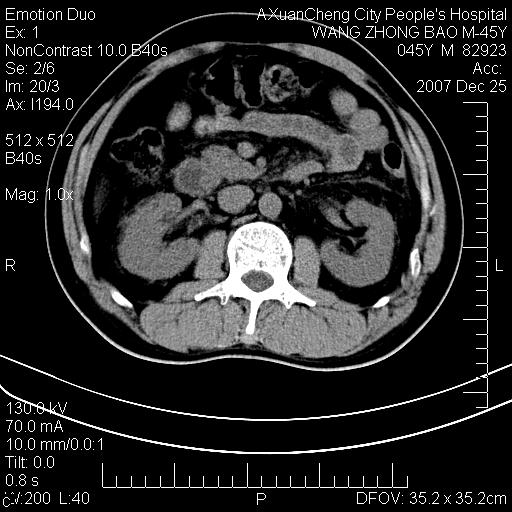

以下是引用qiuleiyu在2007-12-25 18:14:00的发言:[br]胰腺增大,周边渗出改变,肾前筋膜明显增厚,示少量积液.胆囊壁毛糙,周边少许渗出,胆总管壁厚,异常强化,然扩张不明显.结合病程急短;考虑;胆管炎,胆囊炎,胆源性胰腺炎可能大,请结合实验室检查及随访.

以下是引用lisihao在2007-12-25 14:23:00的发言:[br]急性水肿型胰腺炎[br]依据:1、胰腺弥漫性肿大,边缘稍毛糙;[br] 2、双侧肾周筋膜增厚,尤以左侧为甚(重要征象)[br] 3、双侧后胸膜增厚(刺激性炎症);[br] 4、结合病史,查血尿淀粉酶应该可以确诊。